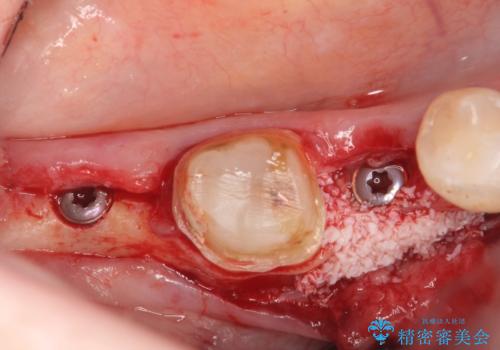

右下7は欠損しており、右下5は保存不可能だったため、インプラントによる欠損補綴を行いました。

インプラント埋入時には骨が不十分な部位に骨増生を行っております。